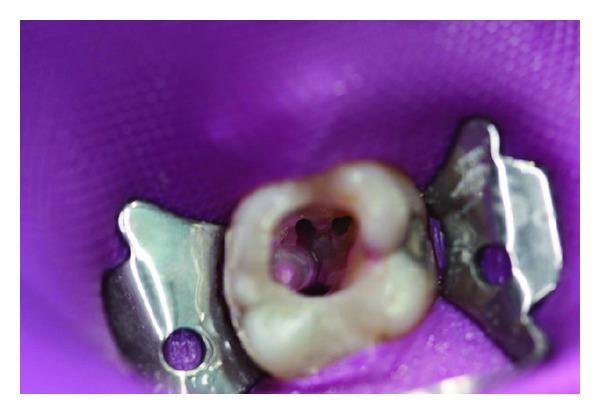

Changes in ambient pressure occur during flying, diving, or hyperbaric oxygen therapy and can cause different types of pathophysiological conditions and pain including toothache (barodontalgia). We report the case of a patient with severe pain in the region of his mandibular left first molar, which had been satisfactorily restored with a conservative restoration. Pain occurred during an airplane flight and persisted after landing. Radiology revealed a periapical radiolucency in the region of the distal root apex. Pain relief was achieved only after endodontic treatment. On the basis of this paper, we investigated the aetiology and management of barodontalgia. Dentists should advise patients to avoid exposure to pressure changes until all necessary surgical, conservative, and prosthetic procedures have been completed. The influence of pressure divergences should be noted at any time. Under changed environment pressures may be the changing perception of pathologies.

在飞行、潜水或高压氧治疗过程中会发生环境压力变化,这可能会导致不同类型的病理生理状况和疼痛,包括牙痛(气压性牙痛)。我们报告了一例患者,其下颌左侧第一磨牙区域疼痛剧烈,该牙已通过保守修复得到满意修复。疼痛在飞机飞行过程中出现,并在着陆后持续存在。放射学检查显示远中根尖区域有根尖周透射区。仅在进行根管治疗后疼痛才得以缓解。基于本文,我们对气压性牙痛的病因及处理进行了研究。牙医应建议患者在所有必要的外科、保守和修复程序完成之前避免暴露于压力变化中。应随时注意压力差异的影响。在环境压力变化的情况下,对病变的感知可能也会发生变化。